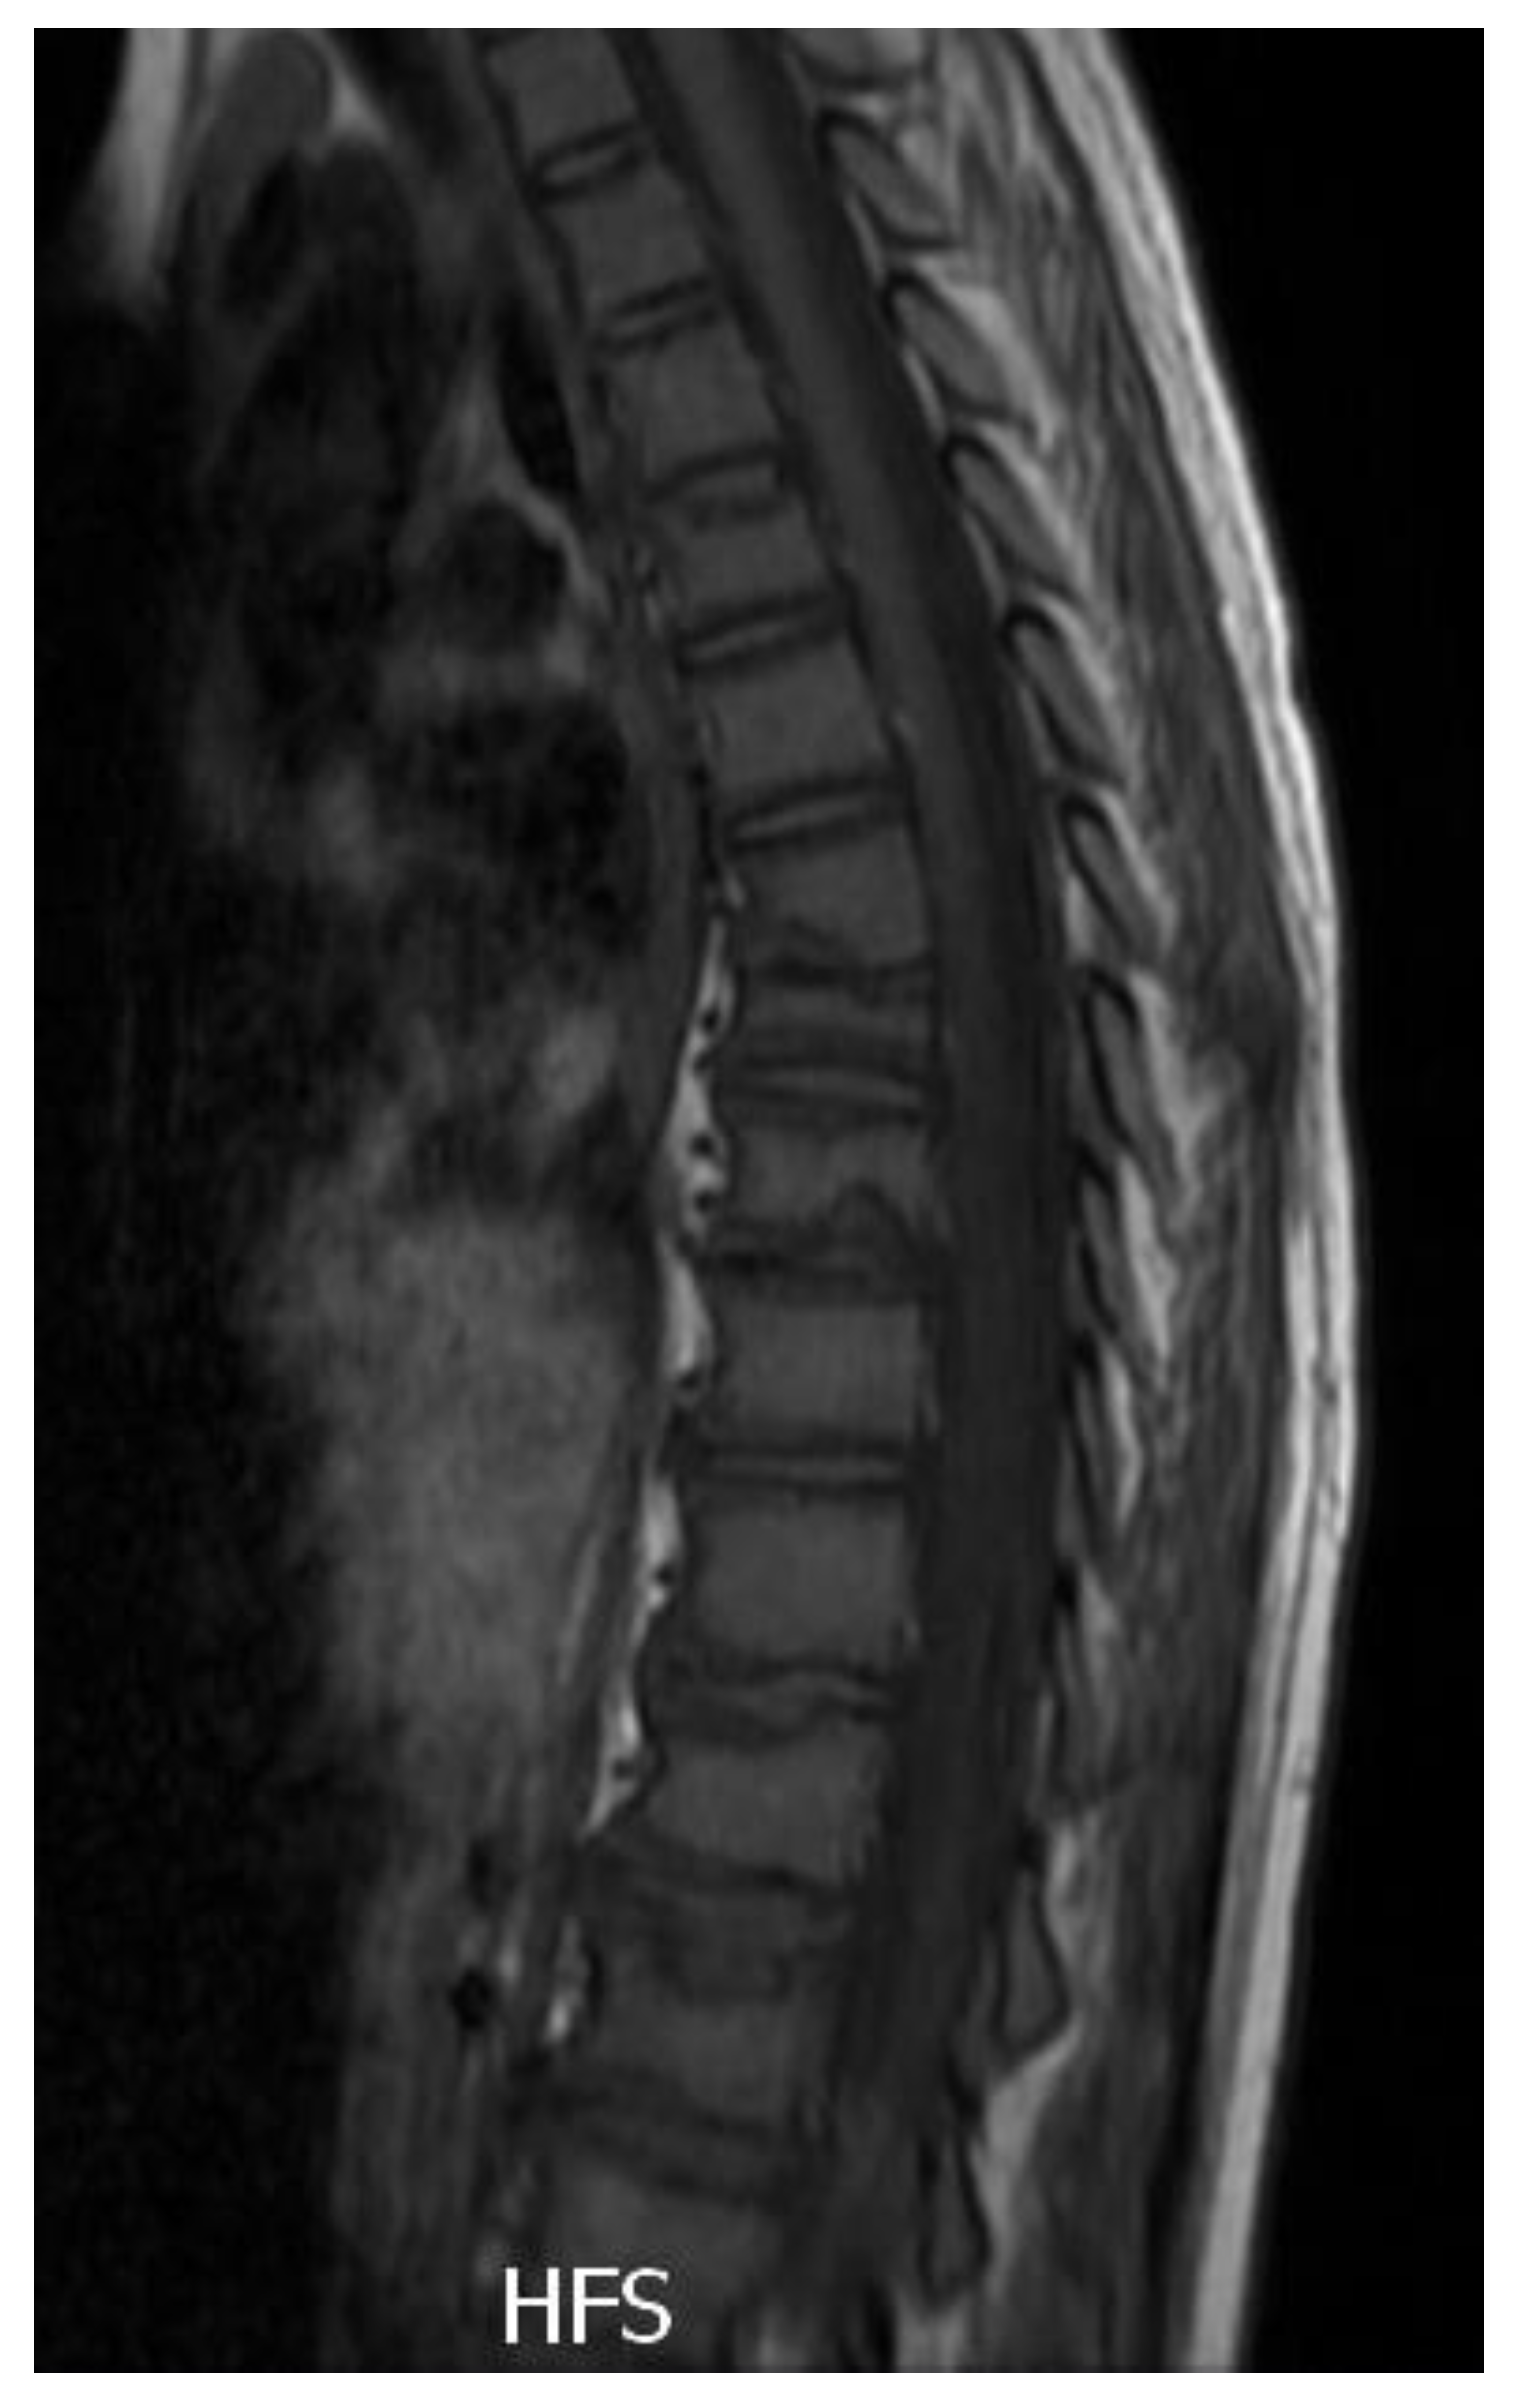

2.3. Diagnostic Assessment

2.4. Therapeutic Intervention

2.5. Follow-Up and Outcomes